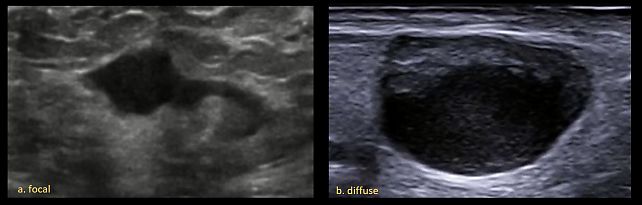

- Cortical thickening (only if medulla is visible): defined as focal (<50% of nodal circumference) or diffuse (>50% of nodal circumference, further categorized as concentric or eccentric) (Figure 5).

5

Lymph node cortical thickening, defined as focal (a) or diffuse (b).